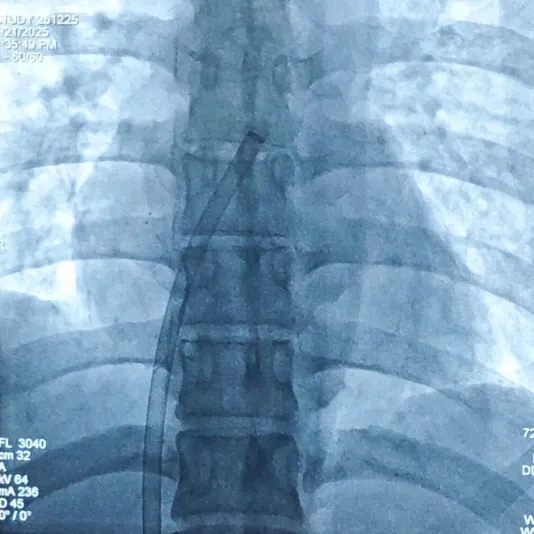

锁定封堵器

封堵器成型,DSA下可见4个Mark点聚拢

锁定后牵拉实验

轻轻牵拉钢缆,4个Mark点依然聚拢在一起

Mark点相对位置未发生变化,并随着钢缆摆动

释放封堵器

钢缆和鞘管同时撤出,成功释放封堵器